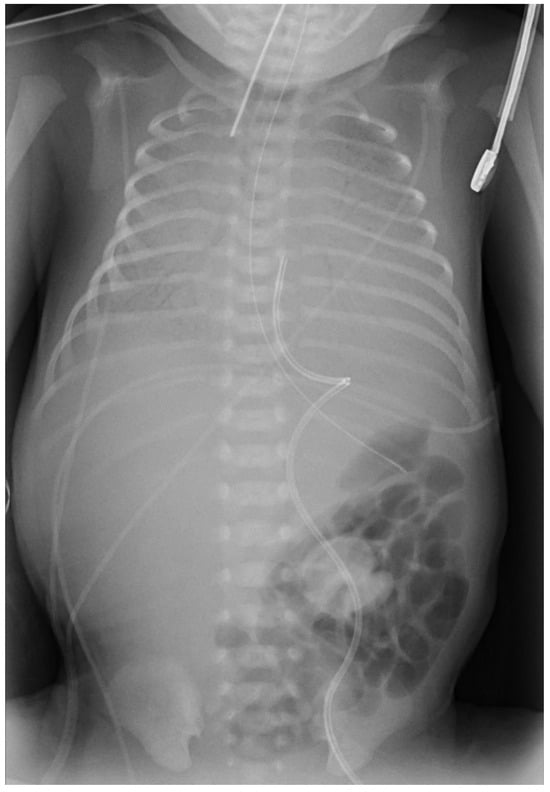

2. Case Report